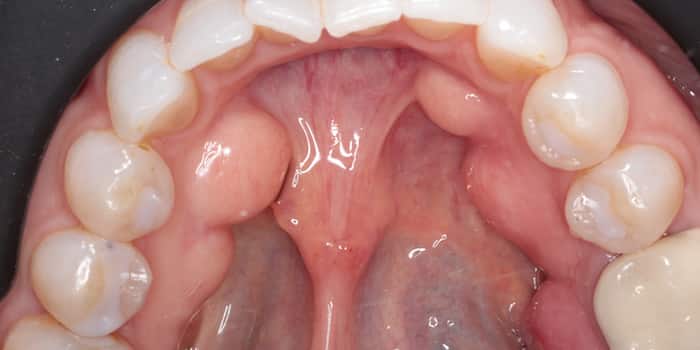

Palatal Torus Removal in Kissimmee, FL

Gentle removal of bony growths on the roof of the mouth for better comfort and oral health

Finding a bony growth in the roof of your mouth can be unsettling, but a Palatal Torus is a benign condition that we resolve with specialized surgical care. While often harmless, these slow growing structures can cause discomfort with dentures, interfere with speaking, or become easily irritated. Our expertise is focused on the precise, gentle removal of the torus, permanently eliminating the source of irritation and restoring smooth, comfortable oral function with minimal recovery time.